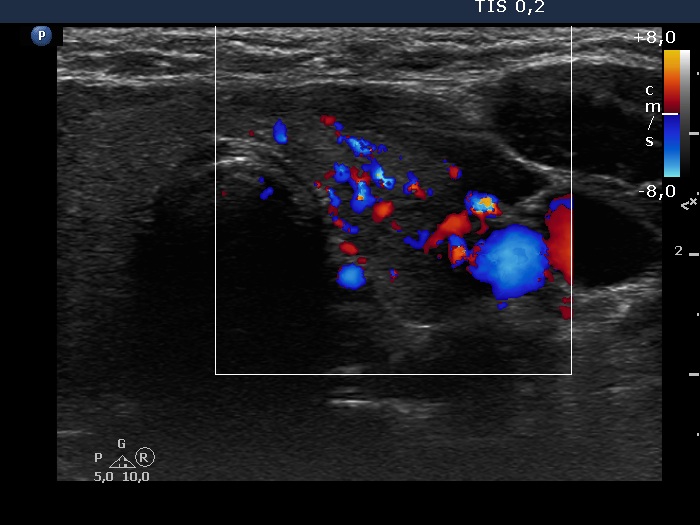

Consecutive patients with the final diagnosis of Hashimoto's thyroiditis - case 4 (1556) (ultrasonographic picture 6)

Left lobe, transverse scan, color Doppler mode. The vascularization is increased.